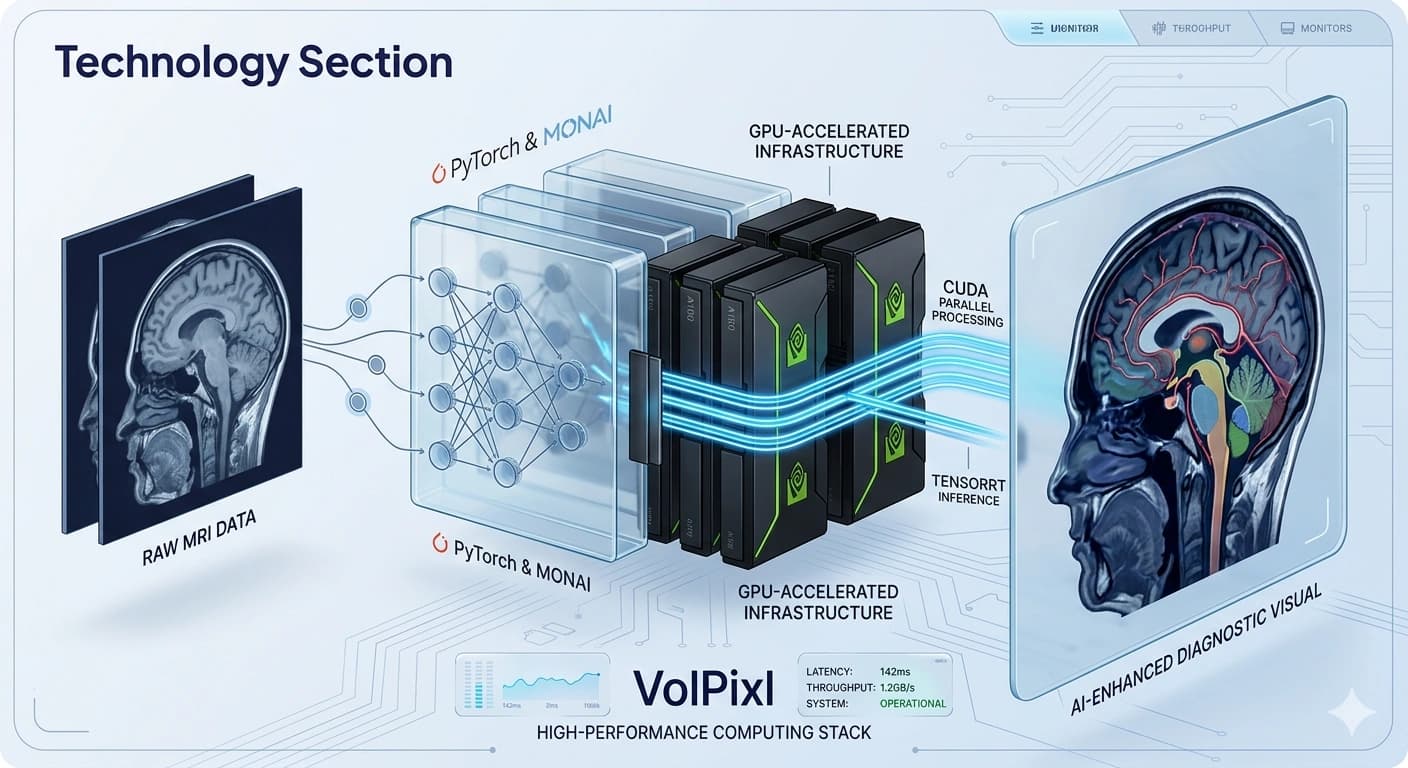

VolPixl's AI models are built using modern deep learning architectures optimized for medical imaging workflows. These models focus on enhancing image quality, identifying regions of interest, and enabling efficient processing of large datasets.

The models are designed to operate within a high-performance pipeline, ensuring fast inference and scalable deployment across different environments.

TensorRT-based inference acceleration

GPU-accelerated execution

PyTorch for model development

MONAI for medical imaging workflows

CUDA-based parallel computation

TensorRT for optimized inference

High-performance GPU infrastructure